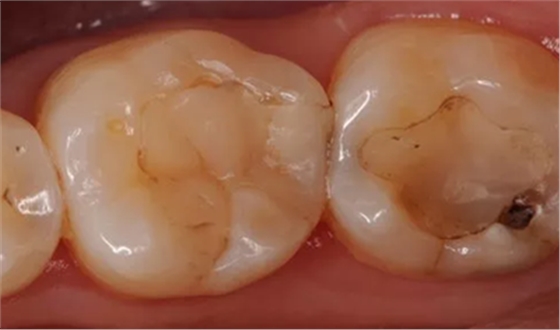

深齲應(yīng)拍攝 X 線片,以協(xié)助了解洞底與牙髓腔的關(guān)系,備洞時(shí)注意避讓。如 PPT2 圖示患者右下五的遠(yuǎn)中和右下六的近中 X 線片上可以看到低密度影像與牙髓組織接觸的很近,這是一個(gè)深齲。